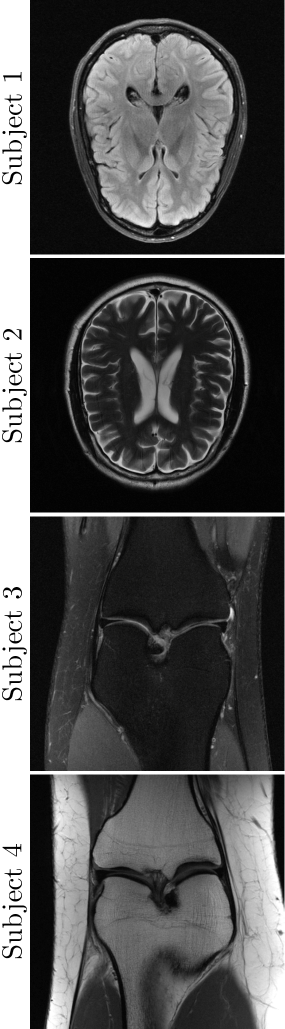

III-A Experimental set-up

In order to evaluate the proposed method, extensive experiments were designed and conducted using a public fastMRI dataset [16] for brain and knee. We obtained 3D k𝑘kitalic_k-space data and MR volume pairs, whose 2D slice dimension is given by 320×320320320320\times 320320 × 320. We simulated the radial undersampling acquisition (4) through non-uniform fast Fourier transformation (NUFFT) to a zero-padded image to the size of 452×452452452452\times 452452 × 452.

For experiments in Section III-B and III-C, the angles of Nφsubscript𝑁𝜑N_{\varphi}italic_N start_POSTSUBSCRIPT italic_φ end_POSTSUBSCRIPT spokes are determined by the golden-angle sampling (46) with R=8𝑅8R=8italic_R = 8 (62 spokes). In Section III-D, we introduce and describe five different sampling schemes including the golden-angle and provide their comparison.

where m𝒳subscript𝑚𝒳m_{\mathcal{X}}italic_m start_POSTSUBSCRIPT caligraphic_X end_POSTSUBSCRIPT and σ𝒳2superscriptsubscript𝜎𝒳2\sigma_{\mathcal{X}}^{2}italic_σ start_POSTSUBSCRIPT caligraphic_X end_POSTSUBSCRIPT start_POSTSUPERSCRIPT 2 end_POSTSUPERSCRIPT represent the mean and variance of {𝒳𝒗}subscript𝒳𝒗\{\mathcal{X}_{\boldsymbol{v}}\}{ caligraphic_X start_POSTSUBSCRIPT bold_italic_v end_POSTSUBSCRIPT }, σ𝒳𝒴subscript𝜎𝒳𝒴\sigma_{\mathcal{X}\mathcal{Y}}italic_σ start_POSTSUBSCRIPT caligraphic_X caligraphic_Y end_POSTSUBSCRIPT denotes the covariance between {𝒳𝒗}subscript𝒳𝒗\{\mathcal{X}_{\boldsymbol{v}}\}{ caligraphic_X start_POSTSUBSCRIPT bold_italic_v end_POSTSUBSCRIPT } and {𝒴𝒗}subscript𝒴𝒗\{\mathcal{Y}_{\boldsymbol{v}}\}{ caligraphic_Y start_POSTSUBSCRIPT bold_italic_v end_POSTSUBSCRIPT }, and c1subscript𝑐1c_{1}italic_c start_POSTSUBSCRIPT 1 end_POSTSUBSCRIPT and c2subscript𝑐2c_{2}italic_c start_POSTSUBSCRIPT 2 end_POSTSUBSCRIPT are constants defined by c1=0.01×(2641)subscript𝑐10.01superscript2641c_{1}=0.01\times(2^{64}-1)italic_c start_POSTSUBSCRIPT 1 end_POSTSUBSCRIPT = 0.01 × ( 2 start_POSTSUPERSCRIPT 64 end_POSTSUPERSCRIPT - 1 ) and c2=0.03×(2641)subscript𝑐20.03superscript2641c_{2}=0.03\times(2^{64}-1)italic_c start_POSTSUBSCRIPT 2 end_POSTSUBSCRIPT = 0.03 × ( 2 start_POSTSUPERSCRIPT 64 end_POSTSUPERSCRIPT - 1 ). In this work, all quantitative values were evaluated by taking an average over 30 test data from non-overlapped subjects.

All experiments were conducted in a computer system with two Intel Xeon CPUs E5-2630 v4 and four NVIDIA GeForce GTX 3080ti GPUs.